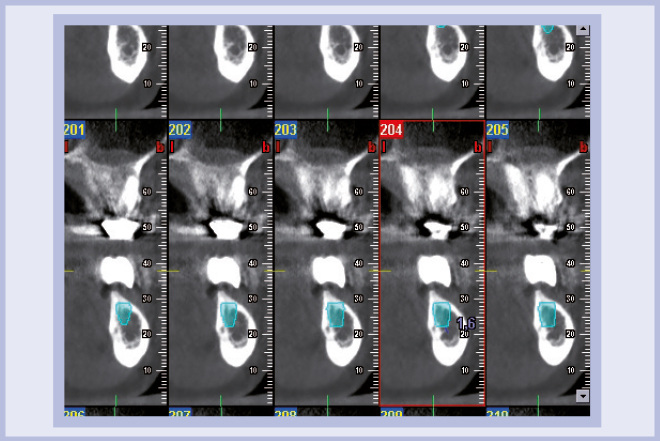

Per riabilitare la masticazione del terzo quadrante, con osso gravemente atrofico, si procede allo studio del caso con esame radiologico 3D e posizionamento virtuale di impianti Exacone® Leone. La prima valutazione è stata eseguita con il software dell’apparecchio radiografico Cone Beam presente in studio. Dopo aver verificato che la quantità di osso residuo fosse sufficiente all’inserimento di due impianti, seppur di dimensioni ridotte, in sede 3.5 e 3.6 senza l’ausilio di tecniche di rigenerazione ossea (Figg. 1-3), si richiede al laboratorio di confezionare una mascherina radiologica con ceratura diagnostica radiopaca e repere standardizzato a livello incisale come da protocollo Leone (Figg. 4, 5). Si verifica quindi clinicamente l’assenza di mobilità della mascherina dopo il posizionamento nel cavo orale del paziente (Figg. 6, 7). Si effettua una CBCT con la mascherina in posizione e l’esame viene inviato in formato DICOM all’azienda Leone assieme al modello master della paziente. L’azienda provvede quindi ad inviare agli Autori il software 3Diagnosys (software di progettazione) in licenza monopaziente con caricati i file DICOM ricevuti; il software viene quindi utilizzato per la progettazione definitiva del caso (Figg. 8-12).

- Figg. 8-12 – Pianificazione implantare con software 3Diagnosys Leone

- Fig. 9

- Fig. 10

- Fig. 11

- Fig. 12